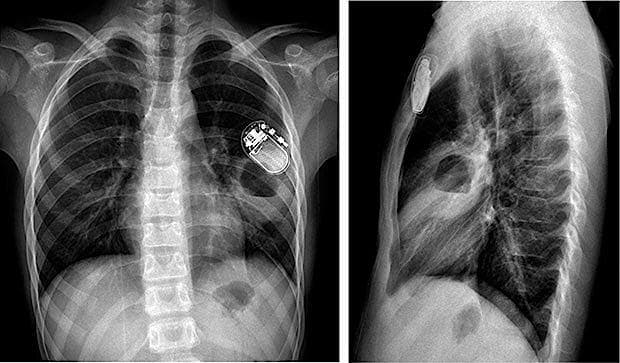

En 13-årig dreng blev indlagt pga. hoste, feber og smerter i brystkassen. Han havde op til indlæggelsen haft influenzalignende sygdom i halvanden uge. Han havde epilepsi og havde fået indopereret en vagusstimulator ca. en måned forinden. Ved indlæggelsen var han febril (temperatur 38,6 °C) og havde let stødende vejrtrækning. Huden var reaktionsløs ved vagusstimulatoren, men lidt kaudalt herfor var han distinkt øm. Blodprøver viste respiratorisk alkalose, et C-reaktivt protein-niveau på 55 mg/l og venstreforskudt leukocytose.

En røntgenoptagelse af thorax viste et rundt infiltrat med central lufttegning på ca. 5 × 5 × 6 cm. Røntgenfundet er typisk for en lungeabsces med central nekrose. Ved en CT bekræftedes diagnosen. Patienten blev sat i behandling med intravenøst givet cefuroxim og metronidazol i to uger og efterfølgende peroralt givet amoxicillin/clavulansyre og metronidazol i to uger, og der blev opnået fuld regression set på en røntgenoptagelse. I modsætning til empyem skal en lungeabsces ikke primært behandles kirurgisk [1].